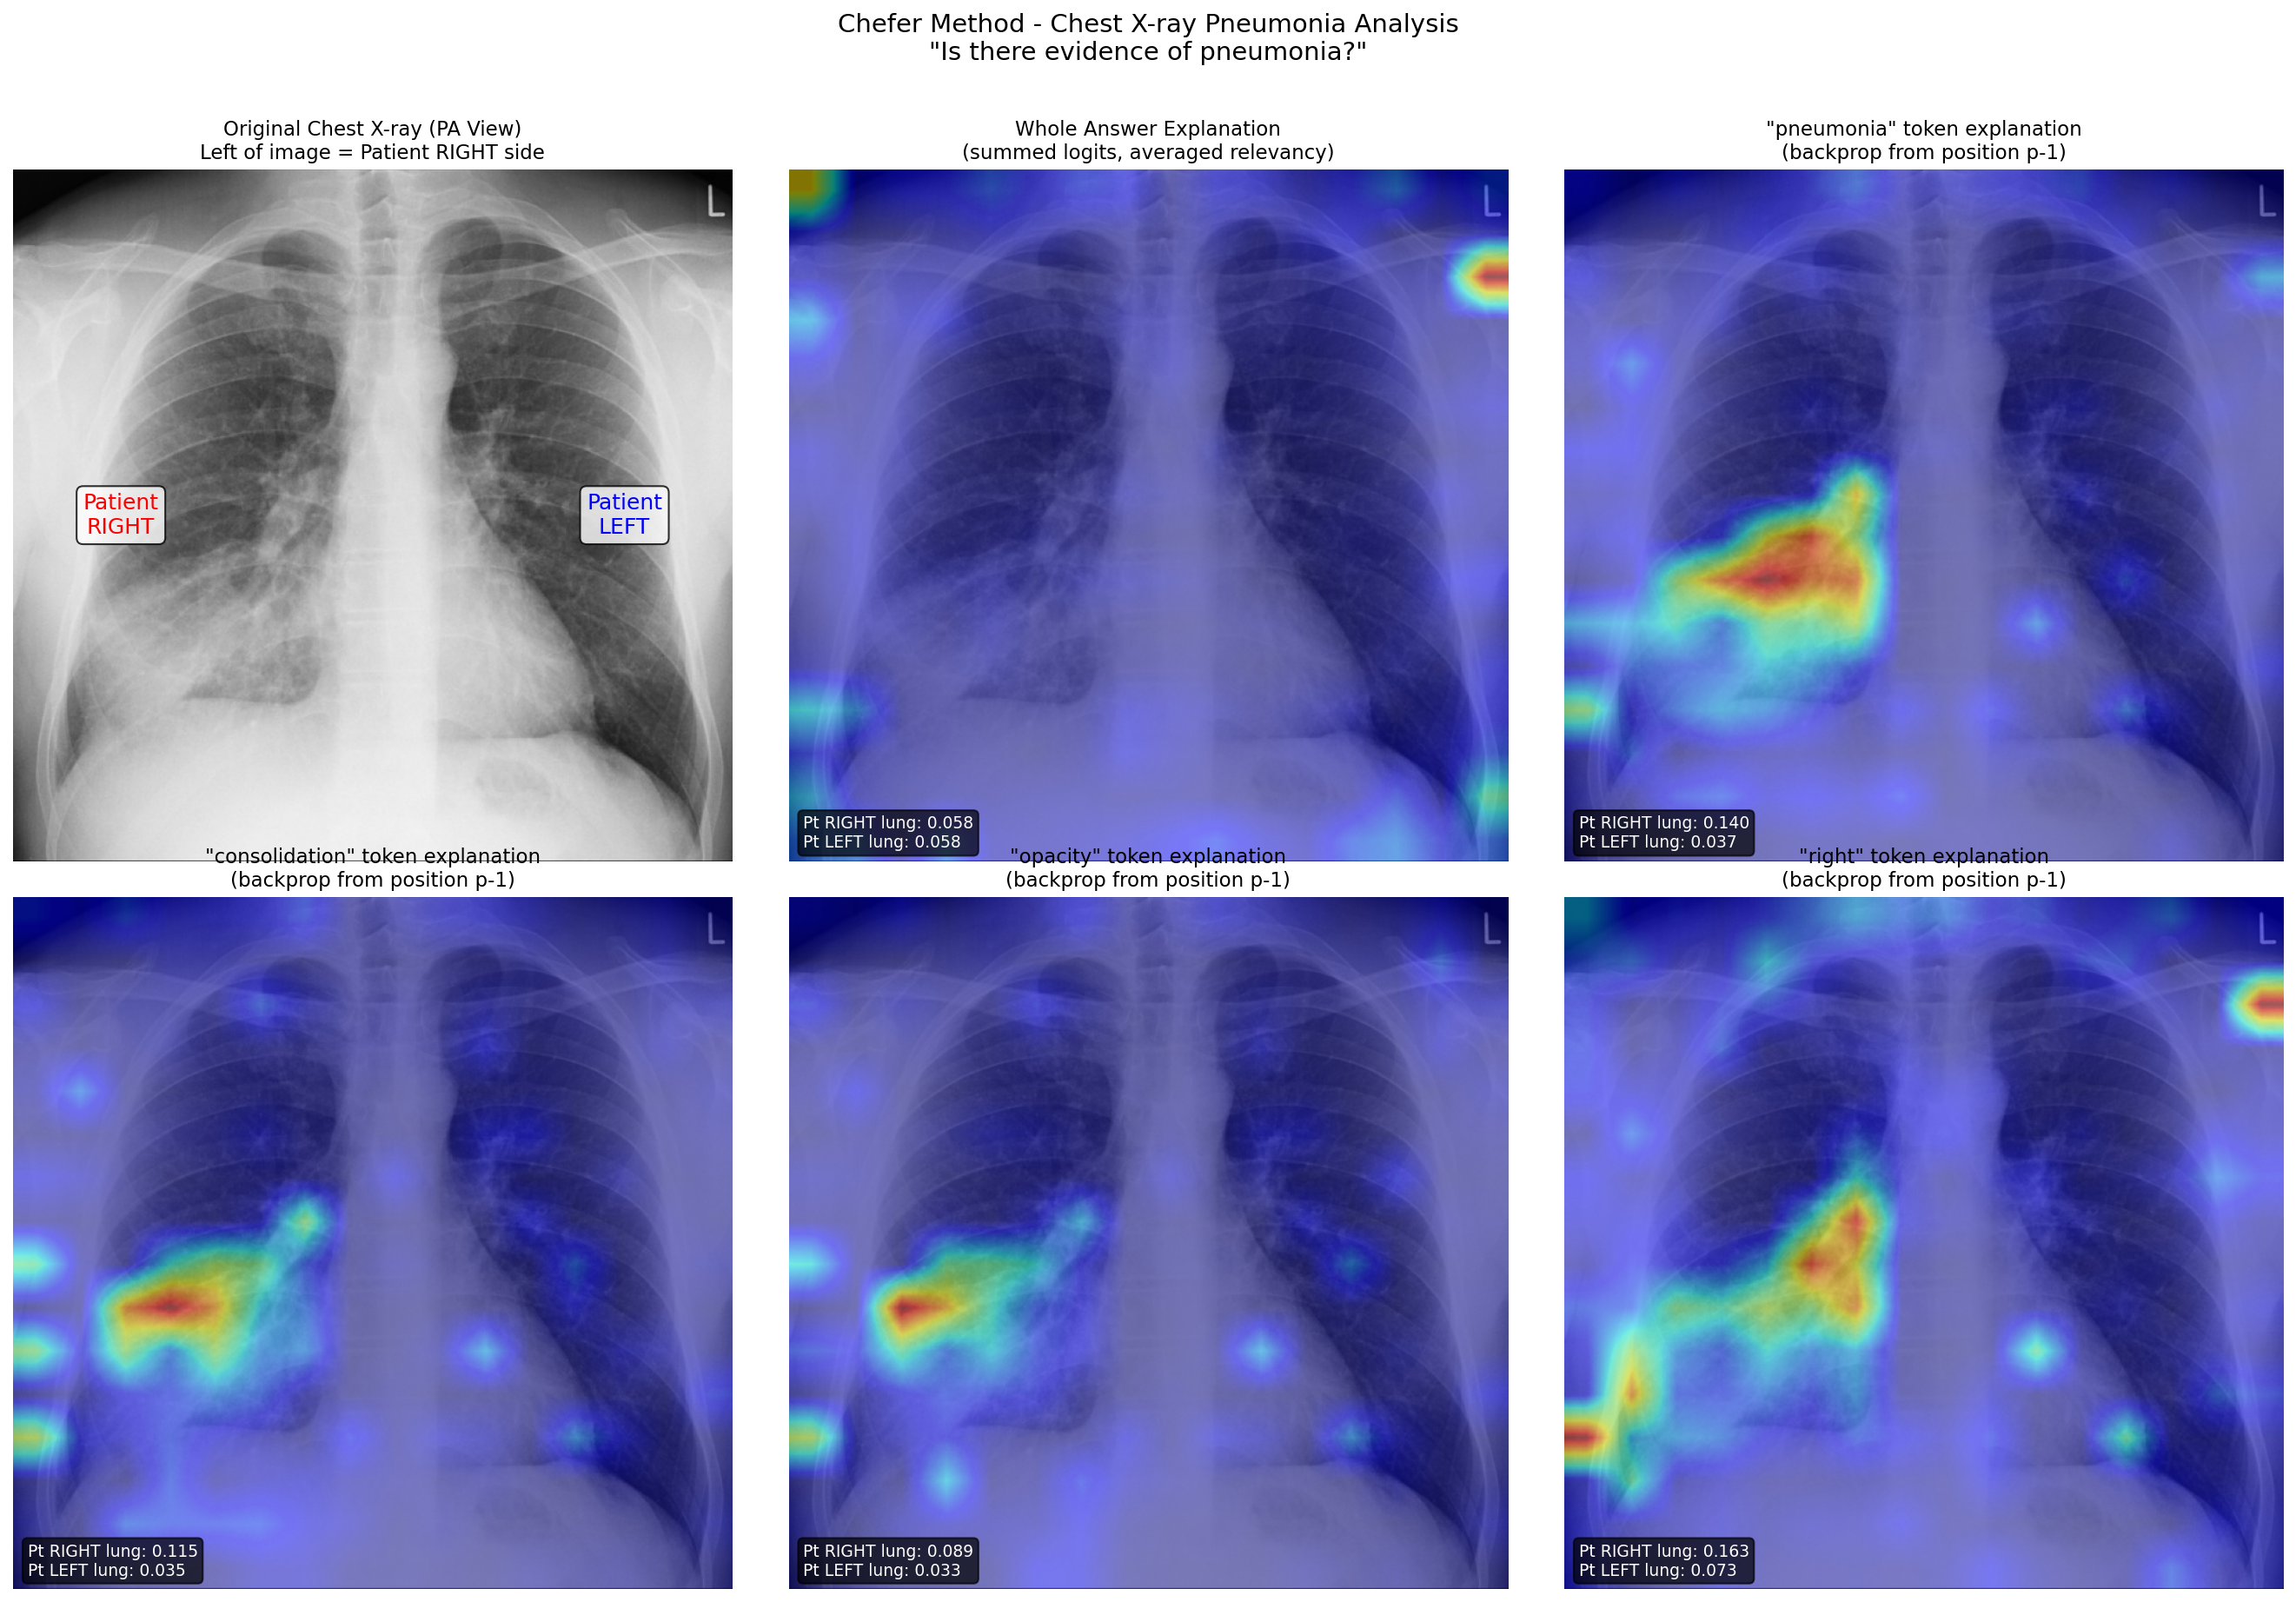

Now for a clinically meaningful example. Here’s a chest X-ray from a patient with right middle lobe pneumonia. A critical detail to understand: in a standard PA (posterior-anterior) chest X-ray, the image is oriented as if you’re facing the patient. This means the left side of the image corresponds to the patient’s RIGHT side.

When I ask MedGemma “Is there evidence of pneumonia?” the model generates a response mentioning consolidation in the right lung. Using the Chefer method, I can explain individual tokens in that response.

Figure 2: Chest X-ray analysis showing token-specific explanations. Top row: original image (with anatomical labels), whole answer explanation, and “pneumonia” token explanation. Bottom row: “consolidation”, “opacity”, and “right” token explanations. Each shows attention correctly focused on the patient’s right lung (left side of image) where the pathology is located.

Look at the “pneumonia” token explanation (top right). The relevancy map shows concentrated attention on the left side of the image, which is the patient’s right lung, exactly where the pathology is located. The quantitative scores confirm this: patient right lung relevancy is 0.140, nearly four times higher than the patient left lung at 0.037.

Even more striking is the “right” token explanation (bottom right of the figure). When the model generates the word “right” (as in “right lung”), the attention is strongly focused on the patient’s anatomical right side. The model isn’t just pattern-matching words; it’s correctly grounding the anatomical term to the corresponding image region.

The “consolidation” and “opacity” tokens show similar patterns, highlighting the area of increased density that characterizes pneumonic infiltration.